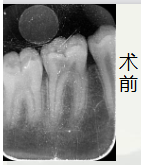

通过术前照与X线片,小牙片可见,颌面龋坏,远中邻面龋坏,叩+,松动-,

夜间自发痛,冷热刺激与对照牙对比反应明显。诊断为急性牙髓炎

开髓后